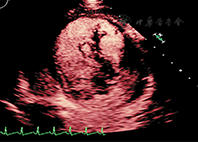

距离探头最近区域和聚焦区域的造影剂微泡破裂严重。如果是实时观察左室影像,由于气泡的破坏可观察到无造影剂增强或心尖区涡流。近场涡流成因是多因素的,主要成因是MI设置过高或注射造影剂剂量不足。通过及时注入新制备的造影剂进入心室腔补充或代替被破坏掉的造影剂的方法可以使涡流伪像消失;如果血流缓慢,新注入的造影剂未能及时充分替代被破坏的造影剂,则在流速最低的区域或高MI时,还会有涡流伪像。生理原因引起的心尖部血流速度超低(严重左心功能不全或心尖部大的室壁瘤)也是涡流伪像的常见原因(图1)。